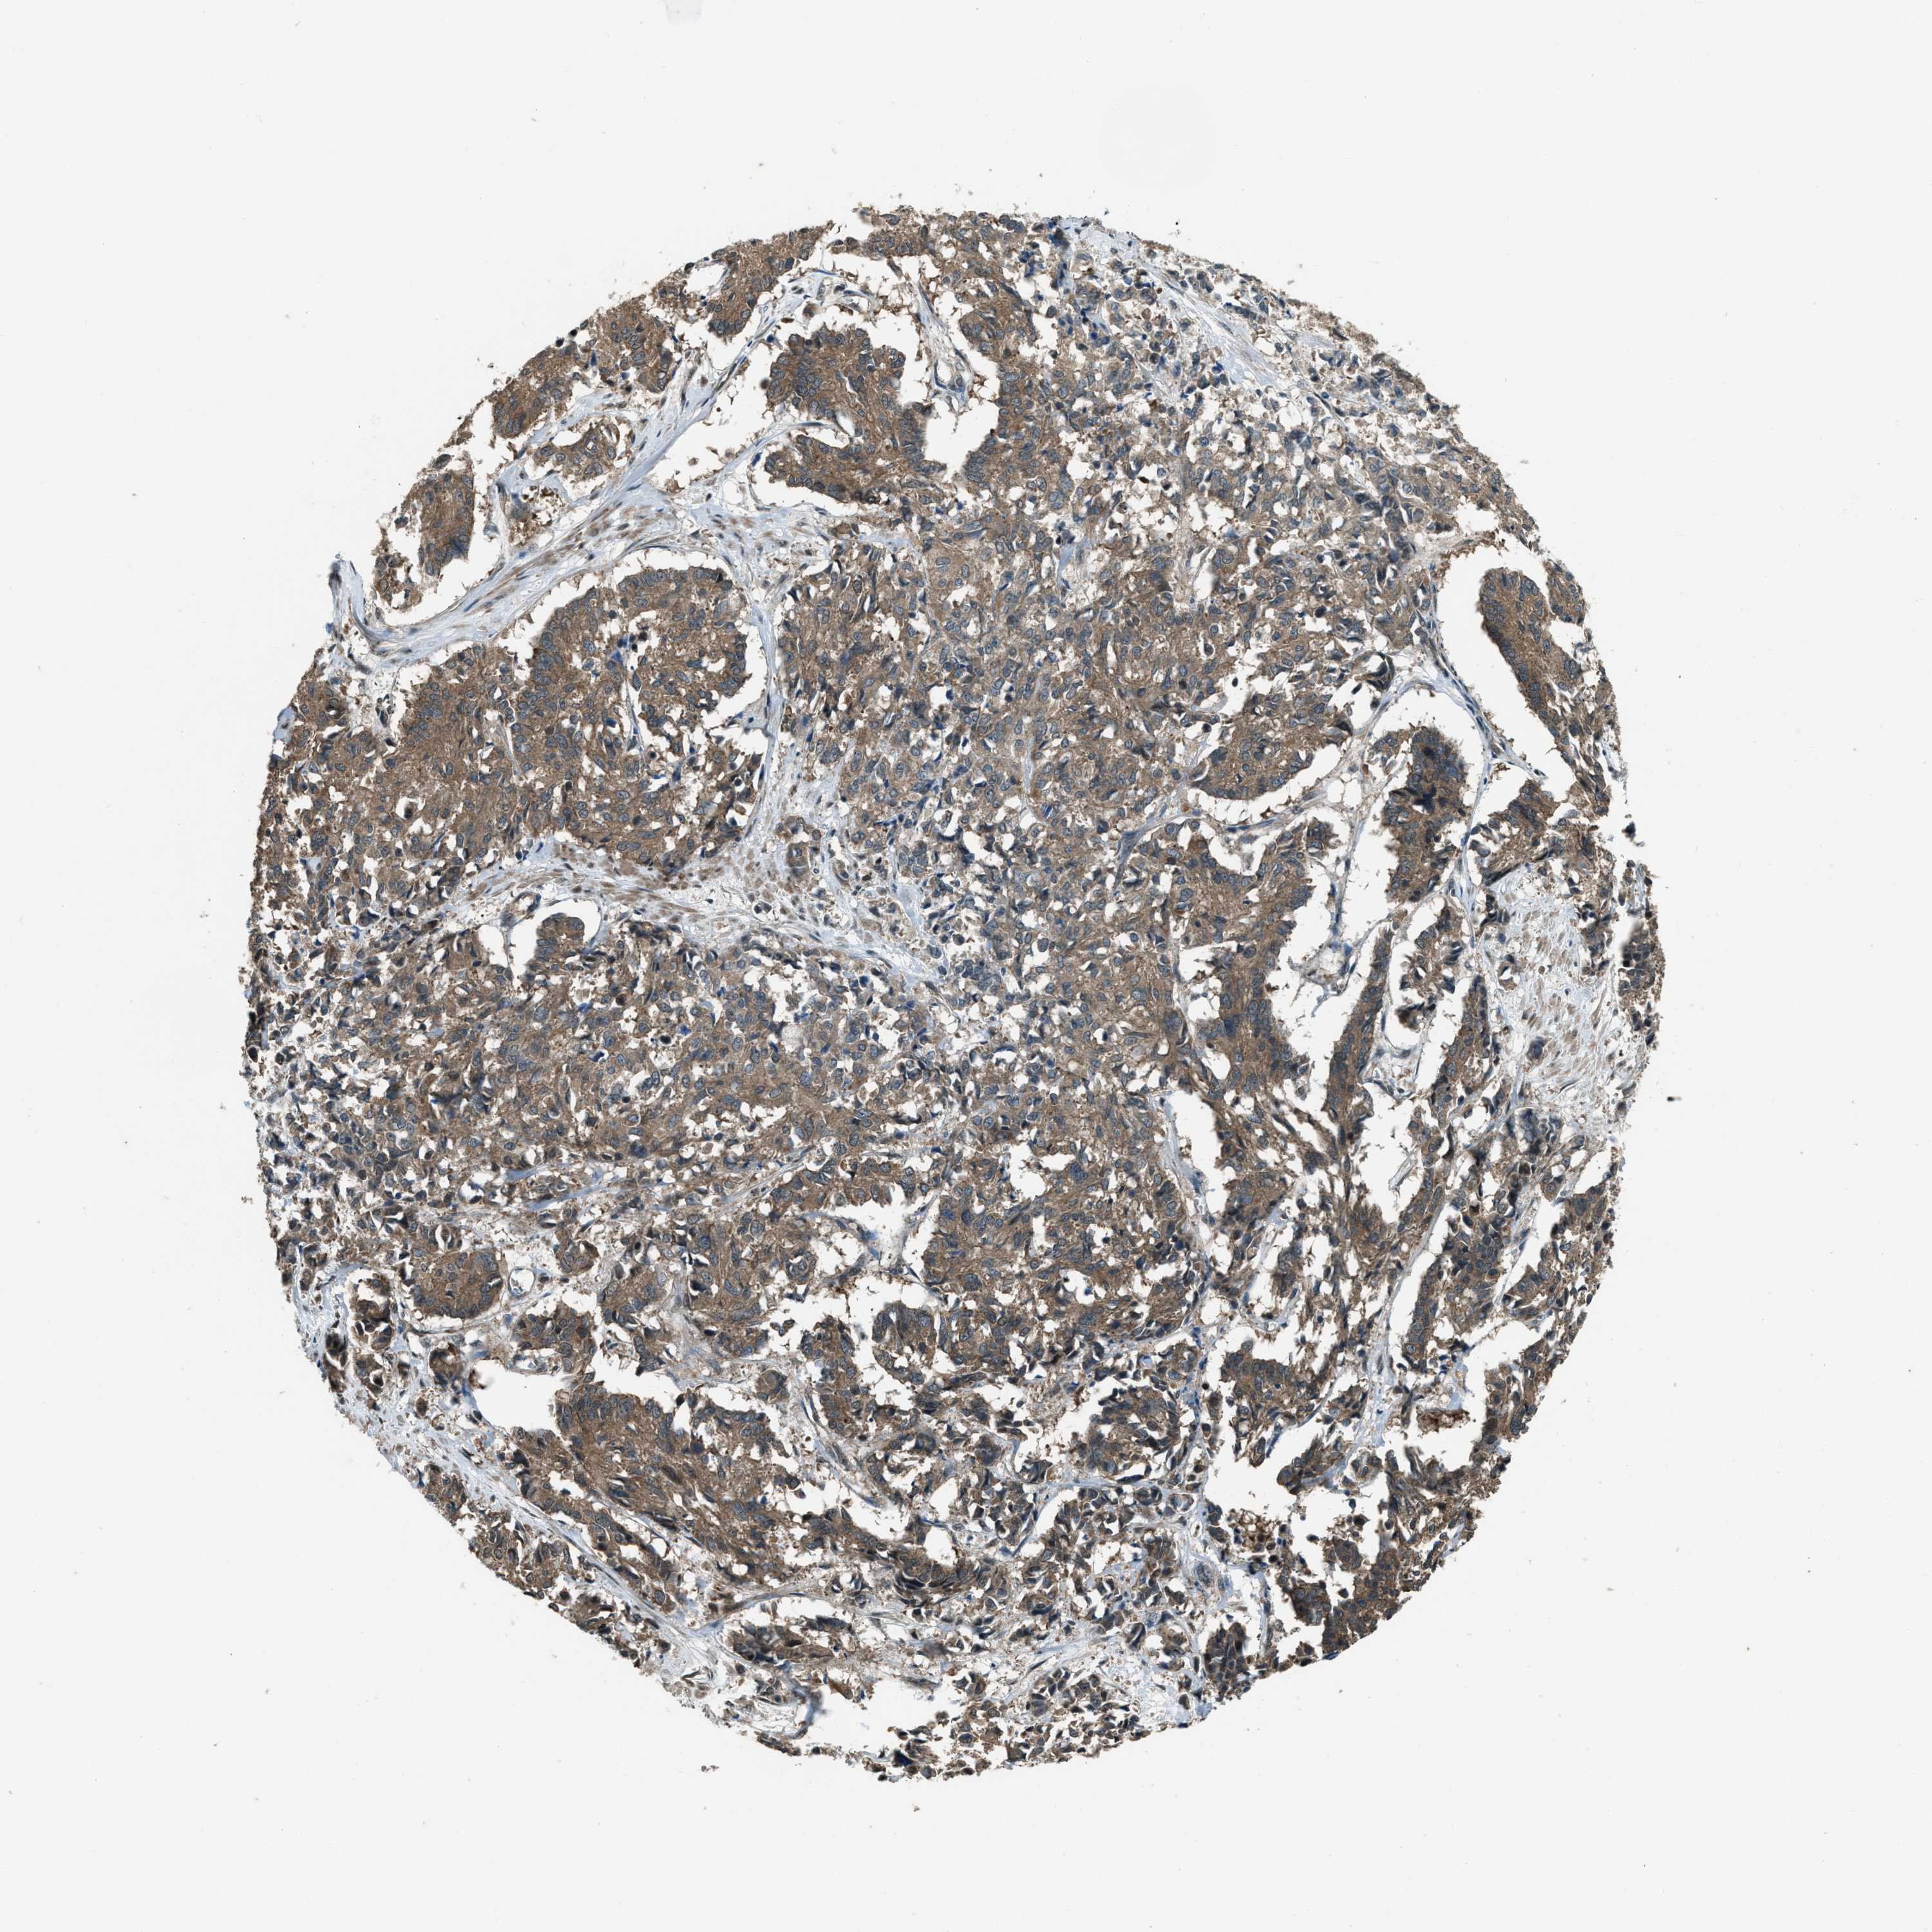

CERVICAL CANCER - Protein expressioni

A mouse-over function shows sample information and annotation data. Click on an image to view it in a full screen mode. Samples can be filtered based on level of antibody staining by selecting one or several of the following categories: high, medium, low and not detected. The assay and annotation is described here.

Note that samples used for immunohistochemistry by the Human Protein Atlas do not correspond to samples in the TCGA dataset.

Antibody stainingi

Antibody staining in the annotated cell types in the current human tissue is reported as not detected, low, medium, or high, based on conventional immunohistochemistry profiling in selected tissues. This score is based on the combination of the staining intensity and fraction of stained cells.

Each image is clickable and will lead to virtual microscopy that enables deeper exploration of all samples and also displays staining intensity scores, fraction scores and subcellular localization as well as patient and tissue information for each sample.

Antibody HPA020095

Antibody HPA020138

Antibody CAB010878

Antibody CAB080402

Squamous cell carcinoma, NOS